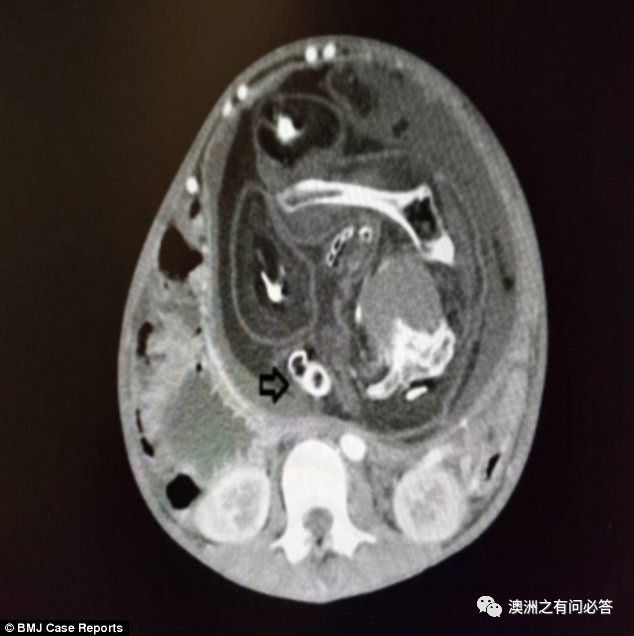

于是医生对男孩进行了腹部CT扫描,

发现果然在男孩腹部,

有一块23.8cm左右大的巨型肿块,

但是这个肿块不像一般肿块,

竟然还有脊椎...